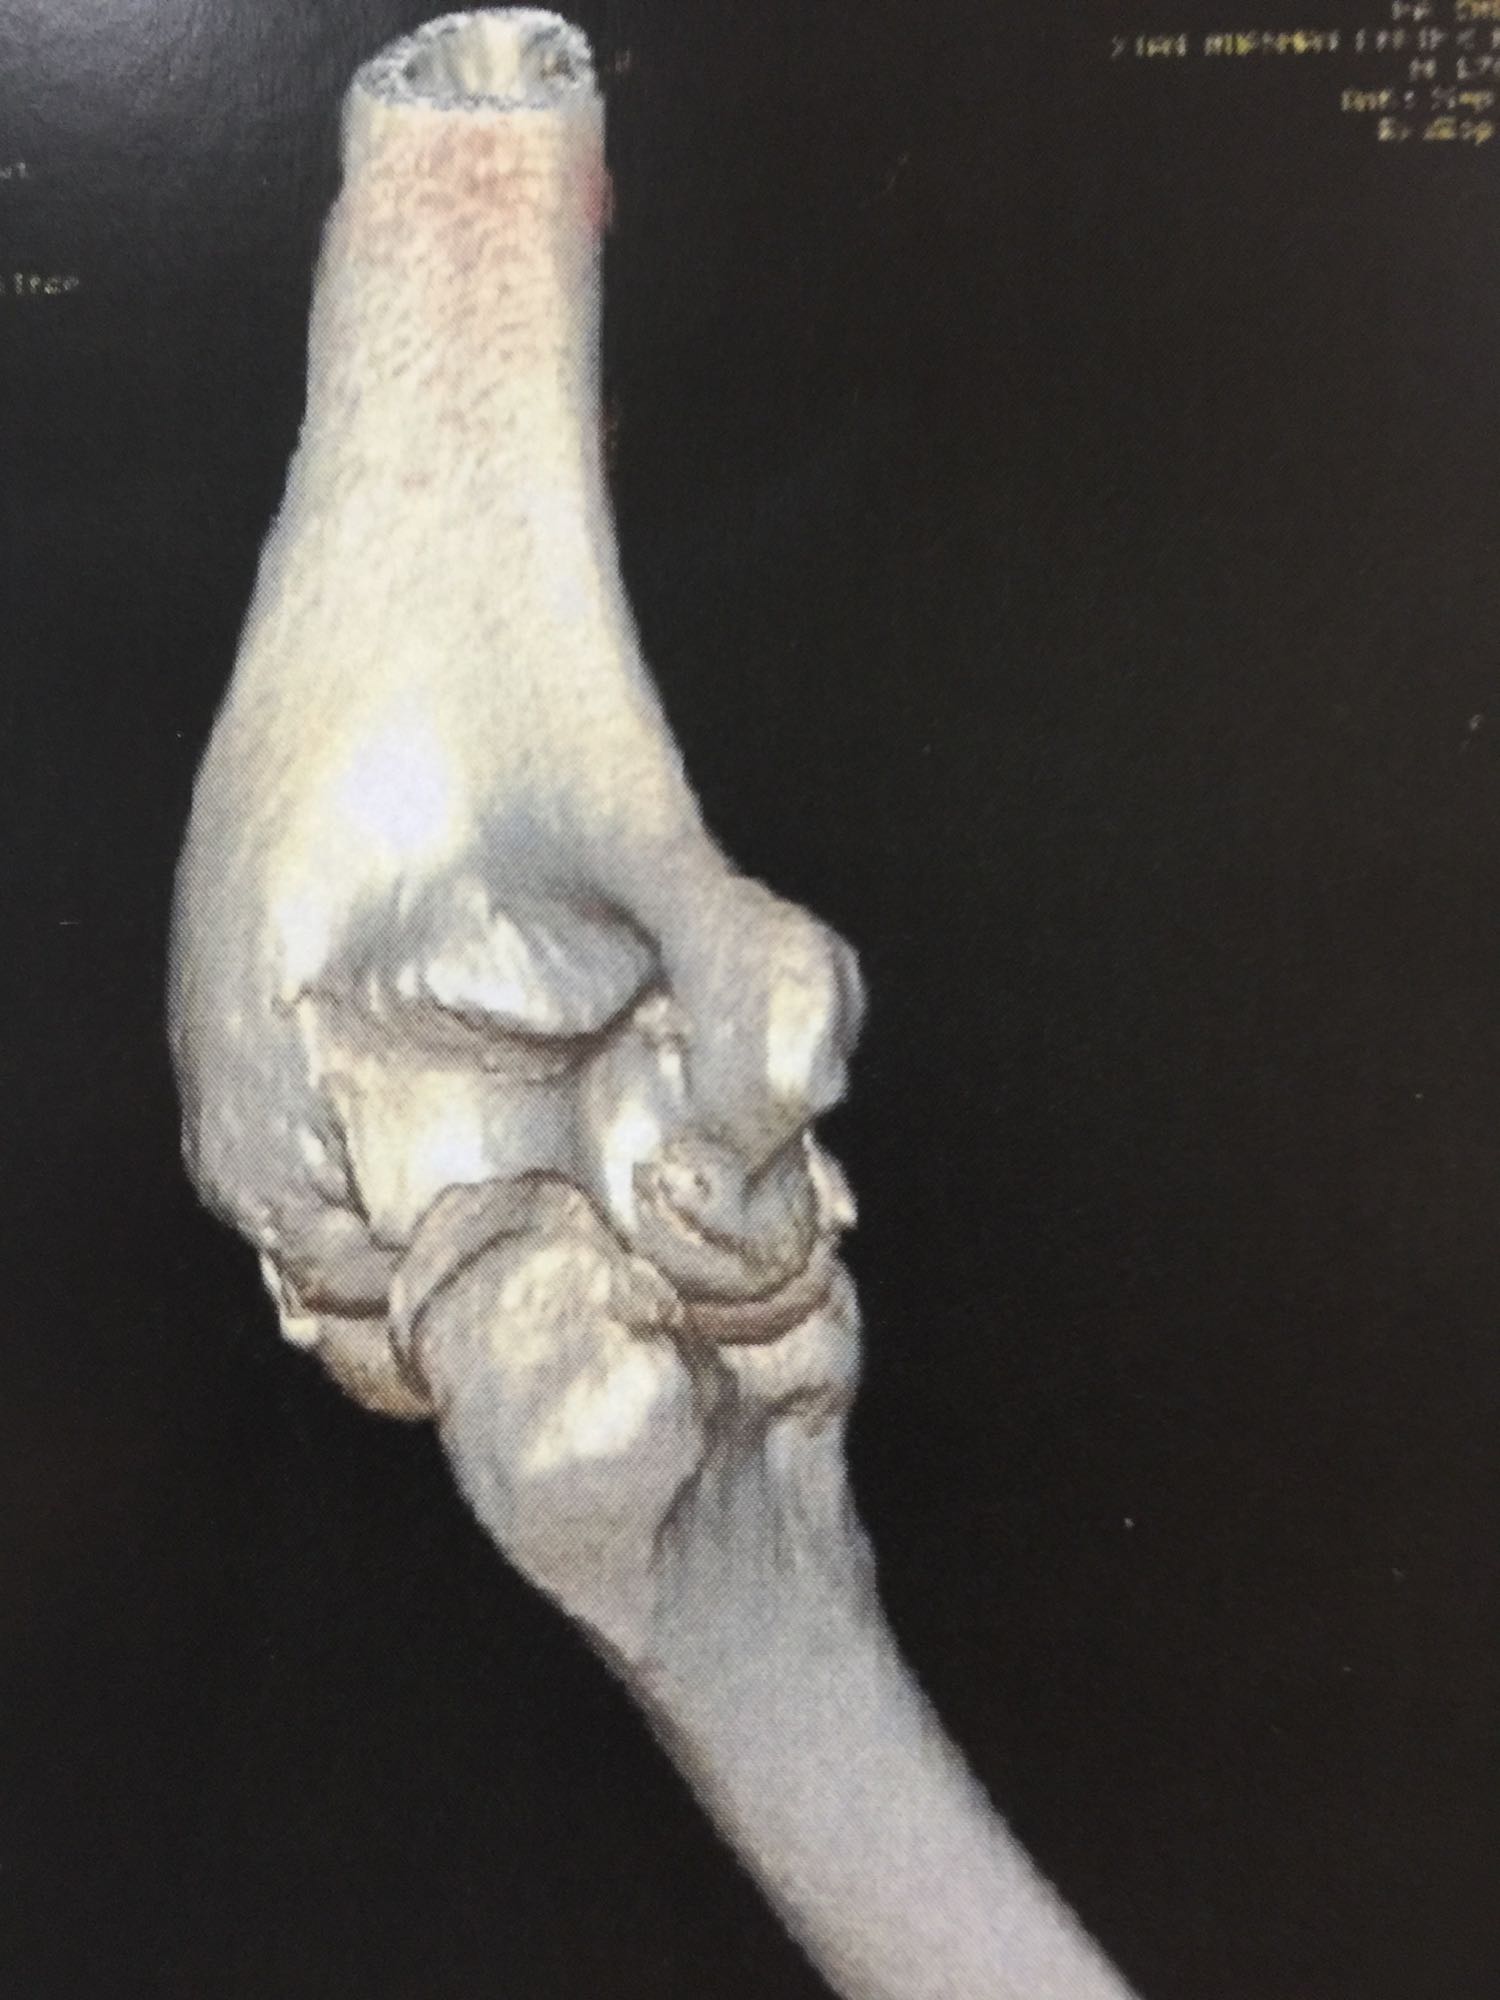

左肘关节高度肿胀,压痛强阳性,肘关节明显活动受限,末梢血运良好,各指关节运动正常。 X线片及CT如图:

1、左尺骨冠状突骨折;2、左肱骨外髁撕脱骨折 治疗:入院后伤肢石膏外固定,给予局部冷敷消肿治疗,于伤后一周行骨折手术治疗,先行前内侧切口复位固定冠状突骨折,活动肘关节发现关节明显不稳定,随取外侧切口,复位固定肱骨外髁,修补外侧副韧带,肘关节明显稳定。术中术后片子如下